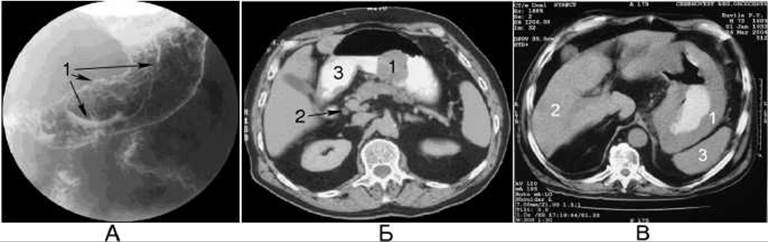

Мал. 183. Рак шлунка. На рентгенограмі шлунка з подвійним контрастуванням (А) виявляється дефект наповнення (1). На комп’ютерній томограмі (Б) виявляється екзофітна форма раку: 1 - пухлина; 2 - лімфатичний вузол; 3 - контрастна маса у шлунку. На комп’ютерній томограмі (В) виявляється ендофітна форма раку: 1 - пухлина; 2 - Печінка; 3 - Селезінка.

Екзофітний рак росте переважно в просвіт шлунка, може бути поліпоподібним і чашоподібним. Поліпоподібні пухлини частіше зустрічаються в ділянці малої кривини та в кардії. Чашоподібна форма раку характеризується припіднятими краями та розпадом у центрі пухлини, розвивається частіше в ділянці великої кривини та в склепінні шлунка. Рентгенознаками екзофітної форми раку є наявність у контрастованому шлунку дефекту наповнення з нерівними контурами (мал. 182, 183). На поверхні чашоподібного раку, у його центрі знаходиться велика виразка - депо контрастної речовини. Складки слизової оболонки обриваються біля краю дефекту наповнення. Ригідність стінки та відсутність перистальтики краще виявляються у випадку локалізації пухлини на краєутворюючому контурі.

Ендофітна форма раку росте переважно внутрішньостінково, може бути виразково-інфільтративною та дифузною (або плоскоінфільтратив- ною, без виразкування). Виразково-інфільтративний рак частіше локалізується у препілоричному відділі та в ділянці малої кривини шлунка. Дифузно-інфільтративний рак локалізується переважно у вихідному відділі, може уражати весь шлунок. Розвиток ендофітної ракової пухлини в шлунку характеризується такими рентгенознаками: появою ригідної ділянки з випрямленими складками слизової оболонки (атиповий рельєф), обривом складок слизової оболонки на краю ураженої ділянки, випрямленням контуру органа та відсутністю перистальтики в ділянці ураження, деформацією органа. Циркулярне поширення ендофітного раку супроводжується звуженням просвіту шлунка.

У разі ендофітної форми раку рентгенівська комп’ютерна томографія є найкращим методом променевого дослідження, за допомогою якого можливо виявити пухлину у вигляді нерівномірного стовщення стінки шлунка з гетерогенним (неоднорідним) посиленням денситометричної щільності після внутрішньовенного контрастування.